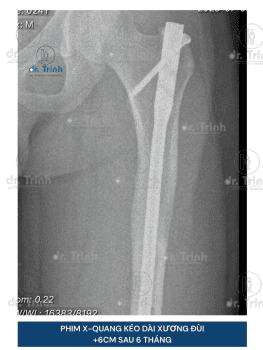

Phẫu thuật kéo dài chân là phương pháp phẫu thuật giúp cải thiện chiều cao giúp cho những người muốn cải thiện chiều cao và vóc dáng. Trong nhiều trường hợp, phẫu thuật kéo dài chân còn giúp điều chỉnh các bất cân xứng chi (chân lệch, chân ngắn bẩm sinh, chênh lệch chiều dài chân sau chấn thương), có thể góp phần mang lại sự cân đối và chức năng vận động tốt hơn.

- Phương pháp phẫu thuật: Đinh nội tủy tự động Precice, khung tròn, khung thẳng mới..

- Vị trí kéo dài: Kéo dài xương đùi hoặc xương cẳng chân có chi phí khác nhau